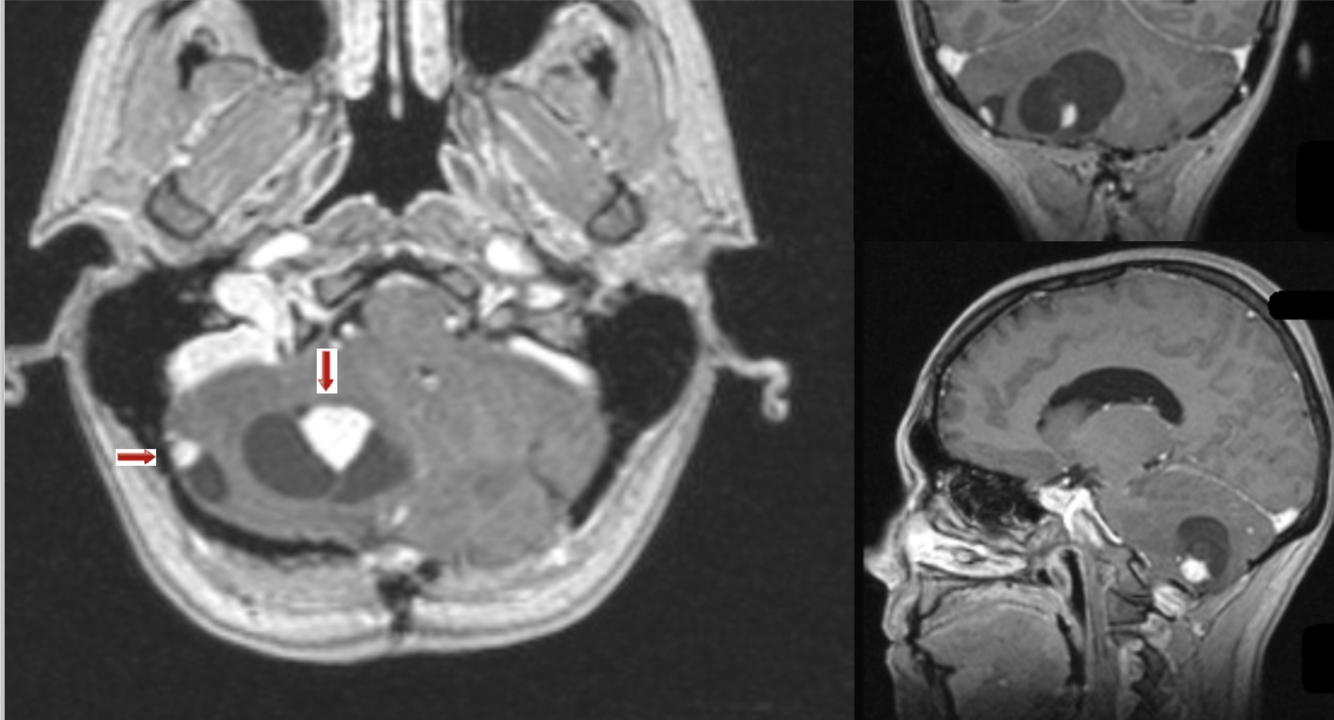

65 y/o M with rigidity.

Olivopontocerebellar atrophy